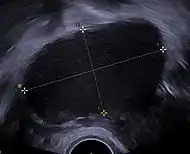

![]() Transvaginal ultrasonography showing a 67 x 40 mm endometrioma as distinguished from other types of ovarian cysts by a somewhat grainy and not completely anechoic content. | |

An endometrioma, endometrioid cyst, endometrial cyst, or chocolate cyst of ovary is a condition related to endometriosis.